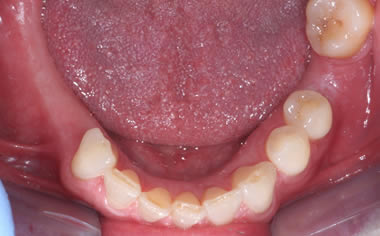

More back teeth replaced by dental implants

Case Three (2 images)